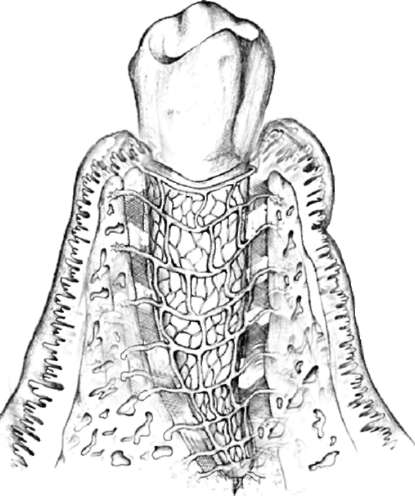

Костная ткань альвеолярного отростка состоит из компактного вещества (система остеонов, костные пластинки), расположенного с оральной и вестибулярной поверхности корней зубов. Между слоями компактного вещества находится губчатое вещество, состоящее из костных трабекул. Костномозговые полости заполнены костным мозгом: красным - в молодом возрасте и желтым жировым - во взрослом. Кроме того, в ткани залегают кровеносные и лимфатические сосуды, а также нервные волокна. Компактное вещество костной ткани альвеолы на всем протяжении корня зуба пронизано системой прободных канальцев, через которые в периодонт проникают кровеносные сосуды и нервы (рис. 4-5, 4-6).

Рис. 4-5. Зуб (рисунок). Сосудистая сеть (Гемонов В.В.)